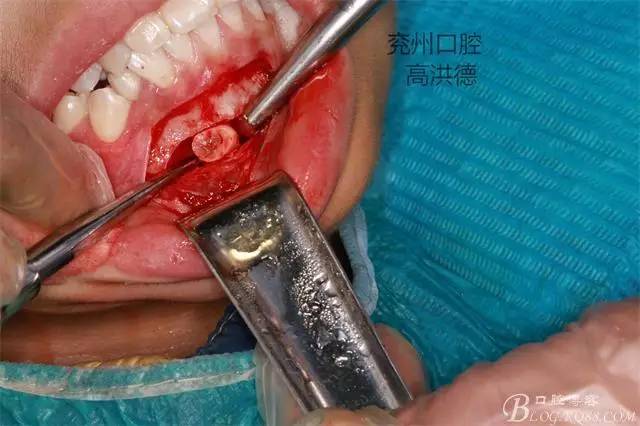

暴露牙齒中端

按設計截斷牙齒